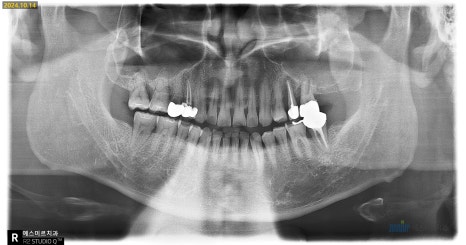

윗니 임플란트의 일반적인 기간이 4개월인데

상당량의 뼈이식을 진행한 케이스라

긴 회복기간이 필요했습니다

약 6개월 후 상악의 뼈가 충분히 단단해진 것을 확인하고

임플란트를 완성해드렸습니다

왼쪽 치료 전, 오른쪽 치료 후